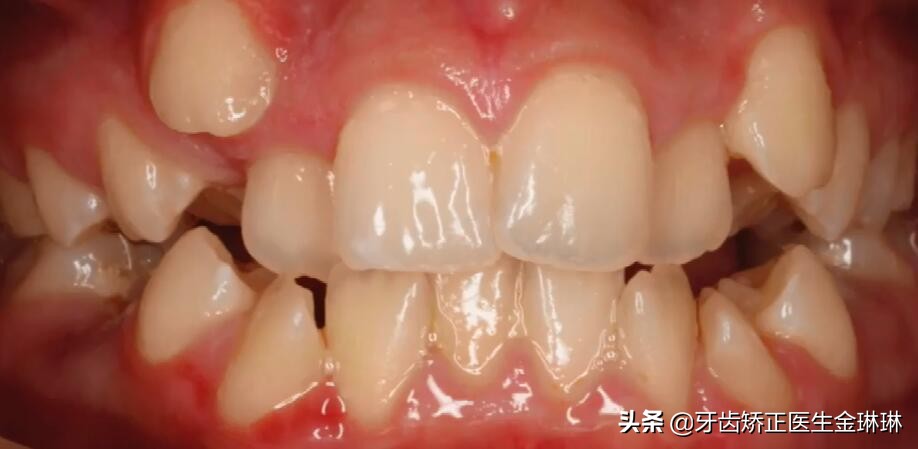

蛀牙,还有前面的牙齿拥挤不齐,不知道能不能矫正?一般来说,是可以通过正畸解决的。那么具体要怎么操作呢?接下来我们详细了解一下。

4颗蛀牙加牙齿拥挤不齐,要怎么矫正

2、再做牙齿拥挤的矫正。